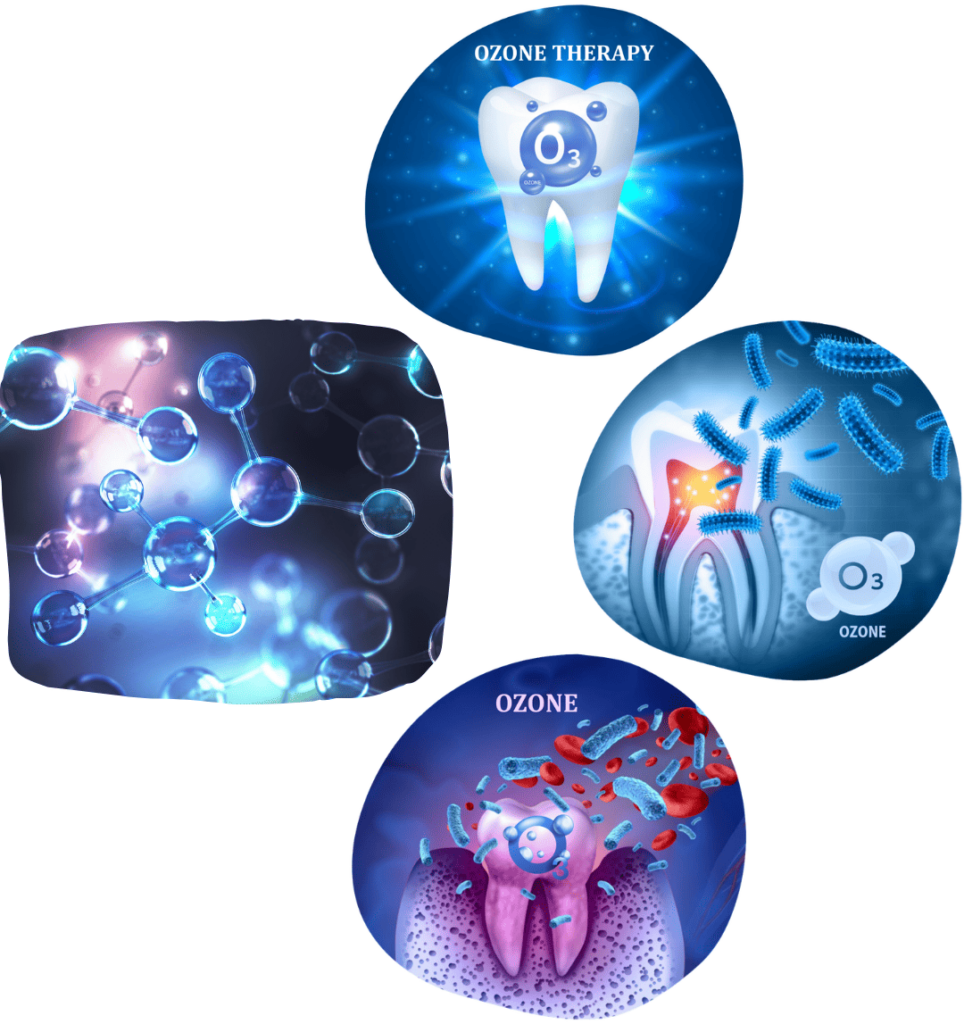

EKSTRAKCIJA ZUBA

Ekstrakcija zuba je zahvat uklanjanja zuba iz čeljusti. Iako uvijek nastojimo sačuvati prirodni zub, u određenim situacijama vađenje je neophodno.

Zahvat se provodi kod teško oštećenih zuba, parodontnih bolesti, nakon traume ili zbog nedostatka prostora za ortodontski tretman.

Ekstrakcije zuba radimo uz minimalnu traumu okolnog tkiva kako bi oporavak bio što bezbolniji i kraći.

Nedostatak zuba narušava stabilnost preostalih zuba, uzrokujući njihovo pomicanje i rotaciju, promjene zagriza, poremećaje u čeljusnom zglobu te ubrzan gubitak kosti, što može ograničiti mogućnosti optimalne terapije.

Zato je jako važno izvađen zub nadoknaditi što prije.

Zube je moguće nadoknaditi ugradnjom implantata, krunicama, mostovima, zubnim protezama ili kombinacijom protetskih nadomjestaka.

Prednost ugradnje zubnih implantata je u tome što ne zahtijevaju brušenje zdravih susjednih zuba, već u potpunosti nadoknađuju izgubljeni zub, čuvaju okolne zube i sprječavaju gubitak kosti.